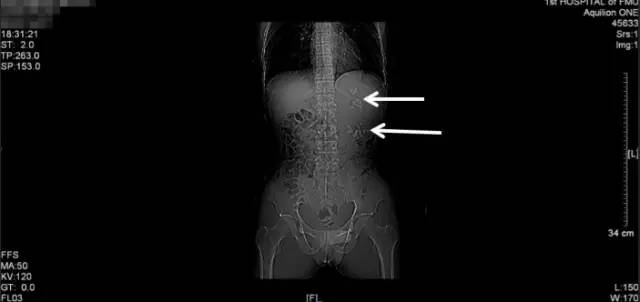

第二次来福建医科大学附属第一医院复查KUB检查结果

通过与4个月前的片子对比,我们可以看到虽然经过了两次手术,但是左肾区仍然遗留了大量而且分散的结石,甚至输尿管上段都有结石卡住(白色箭头所指结石),所以其症状仍然反复。

从他复查的这个KUB上,我们可以看到,左肾仍然有很多结石,而且还有结石掉到左侧输尿管上段引起了梗阻。这种结石如果不取干净,他肾脏里的结石就会时不时掉下来一颗两颗的,堵住输尿管,最终一定会把这个肾脏搞坏掉,我果断通知患者立马住院。

入院后进一步行泌尿系CT平扫+三维重建

(白色箭头提示的就是多发的残留结石)

CT三维重建图像可见左肾明显增大、扩张积水、多发结石